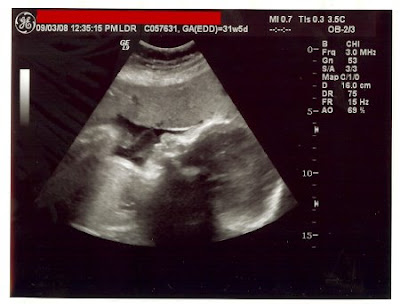

Sorry to complain. I'm down to 60 days, so ya'all only have to put up with the preggy side of me for that much longer. Think we can make it?! ;)